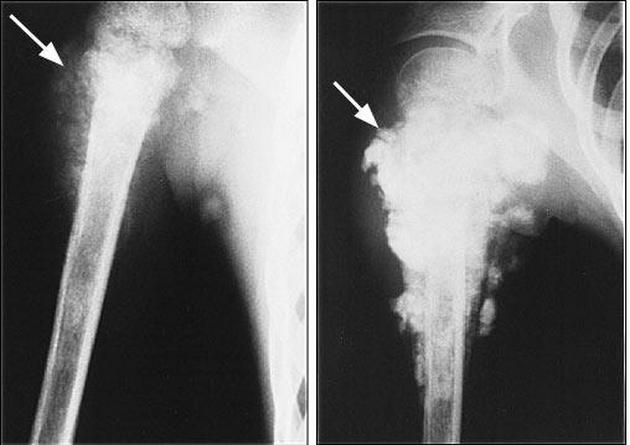

Опухоль может возникнуть в костях таза – это заболевание носит название «остеосаркома». Человек ощущает боль во всей тазовой области. Женщине при подозрении на такую болезнь стоит наблюдаться у онколога, предварительно диагностировав возможный диагноз при помощи МРТ или КТ.

Остеосаркома – довольно страшное заболевание, которое помимо проблем с костями несет и боль в копчике

- Опухоли. В крестцово-копчиковой области могут образовываться доброкачественные опухоли, нередко перерождающиеся в злокачественные новообразования. Также иногда в копчике возникают метастазы опухолей, расположенных в соседних органах. Карциномы могут возникать в прямой кишке, возле заднего прохода. Первое время патология проявляется дискомфортом, который постепенно перерастает в боль. Болевой синдром сначала имеет ноющий характер, а затем его интенсивность увеличивается. При раке прямой кишки помимо боли возле копчика наблюдается ухудшение общего состояния, резкое снижение массы тела, гипертермия. Иногда возникает анальное кровотечение.